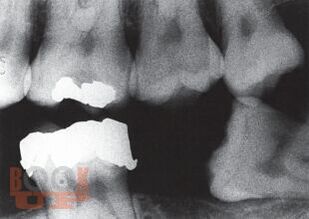

В уникальном компактном руководстве под редакцией авторитетного американского автора детально рассмотрены все основные разделы практической стоматологии, с точки зрения диагностики и лечения экстренных состояний. В руководство включены также главы о механизмах возникновения и диагностике зубной и оро-фациальной боли, организации неотложной стоматологической помощи в офисе, приложение с прописями лекарственных средств, применяемых в стоматологии. Особый интерес представляет информация о самых современных методах, терминах, технических устройствах и материалах, применяемых стоматологами США.